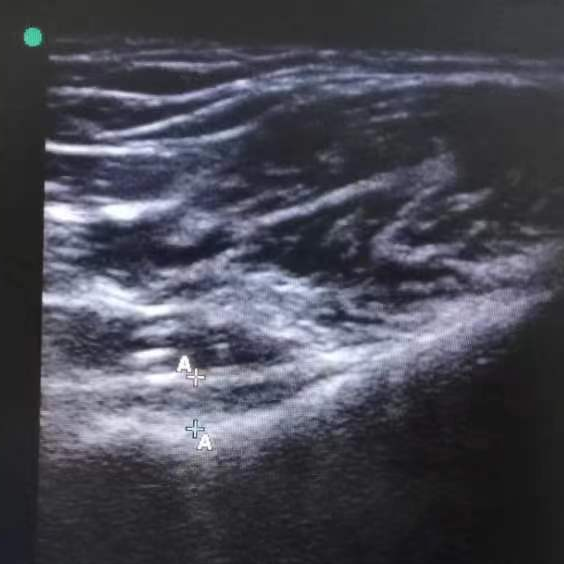

1. 超声引导精准定位

高频超声探头可清晰显示肩关节囊的结构,动态监测穿刺针位置,确保液体精准注入目标区域,避免损伤血管、神经及肌腱。